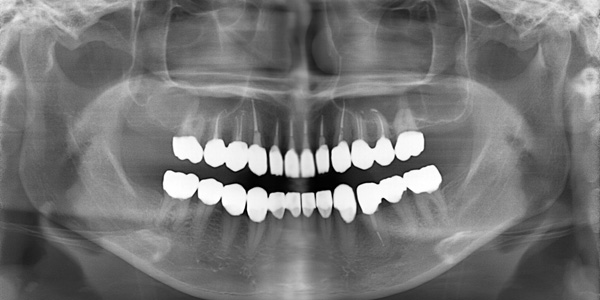

患者さんは40代の女性で、前歯(左上1番)に痛みをともった違和感があり名取歯科医院にご来院されました。写真で見ると一見なんの問題もなく見えますが、レントゲン撮影をすると隣接部分から大きな虫歯が進行していました。 自分の歯を残したいとご希望を頂きましたが治療しても歯が長持ちしない状態で、患者さんのご承諾のうえで抜歯となりました。患者さんの通院のご希望に沿いながら、約2年間でインプラント治療を終えました。